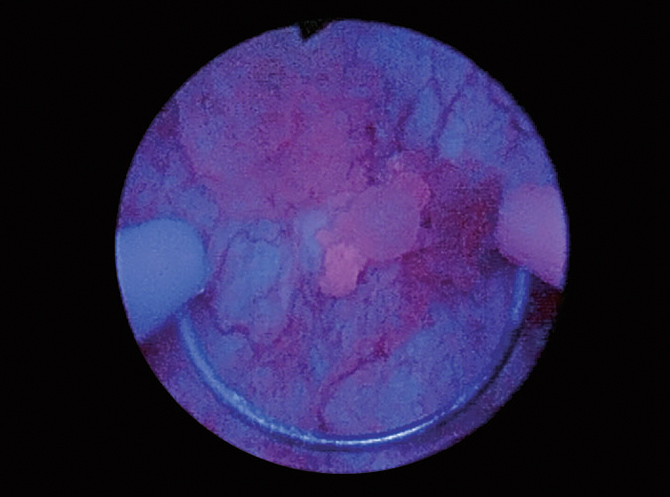

Case 9 Incrustated necrotizing cystitis Male, aged 67

History

67 yo with history of external beam radiotherapy of the prostate (72 Gys). NMIBC was detected four years after and treated by TURB and adjuvant mitomycin C. Patient complains of recurrent UTIs and presents suspicious urine cytology. Cystoscopy shows dense and slightly exophytic fluorescent foci set on an atrophic mucosa.